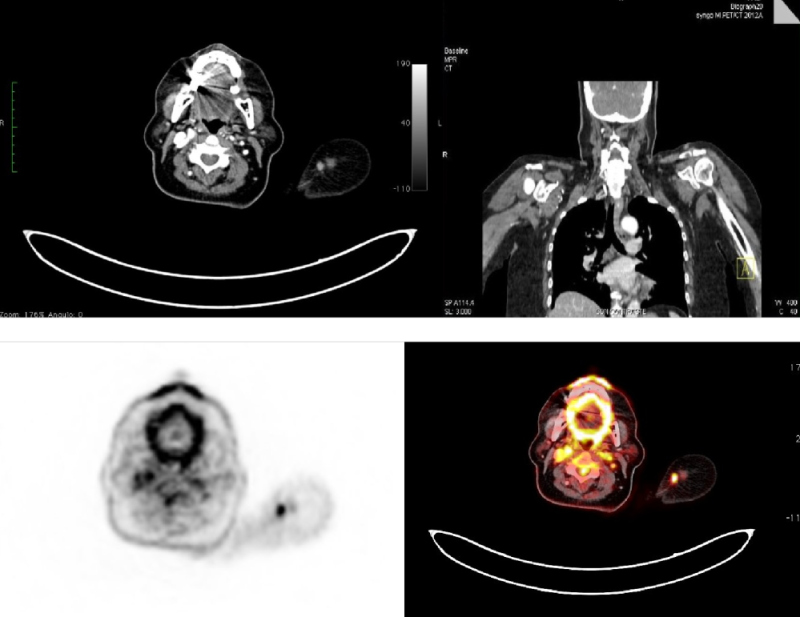

Se realiza PET-CT de etapificación con 18F-FDG, donde se observa un nódulo subcutáneo sólido de 11 mm, bien delimitado, condensidad de partes blandas, ubicado en hombro izquierdo adyacente a la articulación acromioclavicular. Se evidencia aumento del metabolismo glucídico (SUVmax = 3,2) (Fig. 2) y una adenopatía supraclavicular ipsilateral de 15 mm, hipermetabólica (SUVmax = 3.5) (Fig. 3). El resto de la exploración no mostró lesiones hipermetabólicas (Fig. 4).